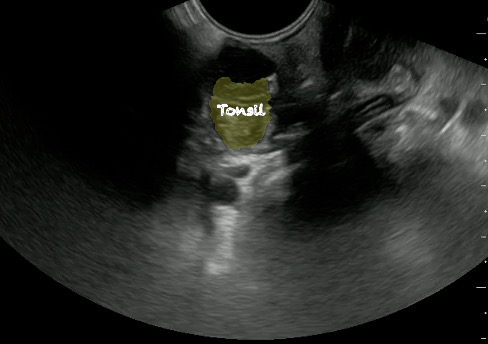

- Normal Tonsil

- The ovoid tonsils appear striated with hyperechoic bands and hypoechoic parenchyma, as well as lobulated margins.

- Figure 42 and 43. Normal Tonsil